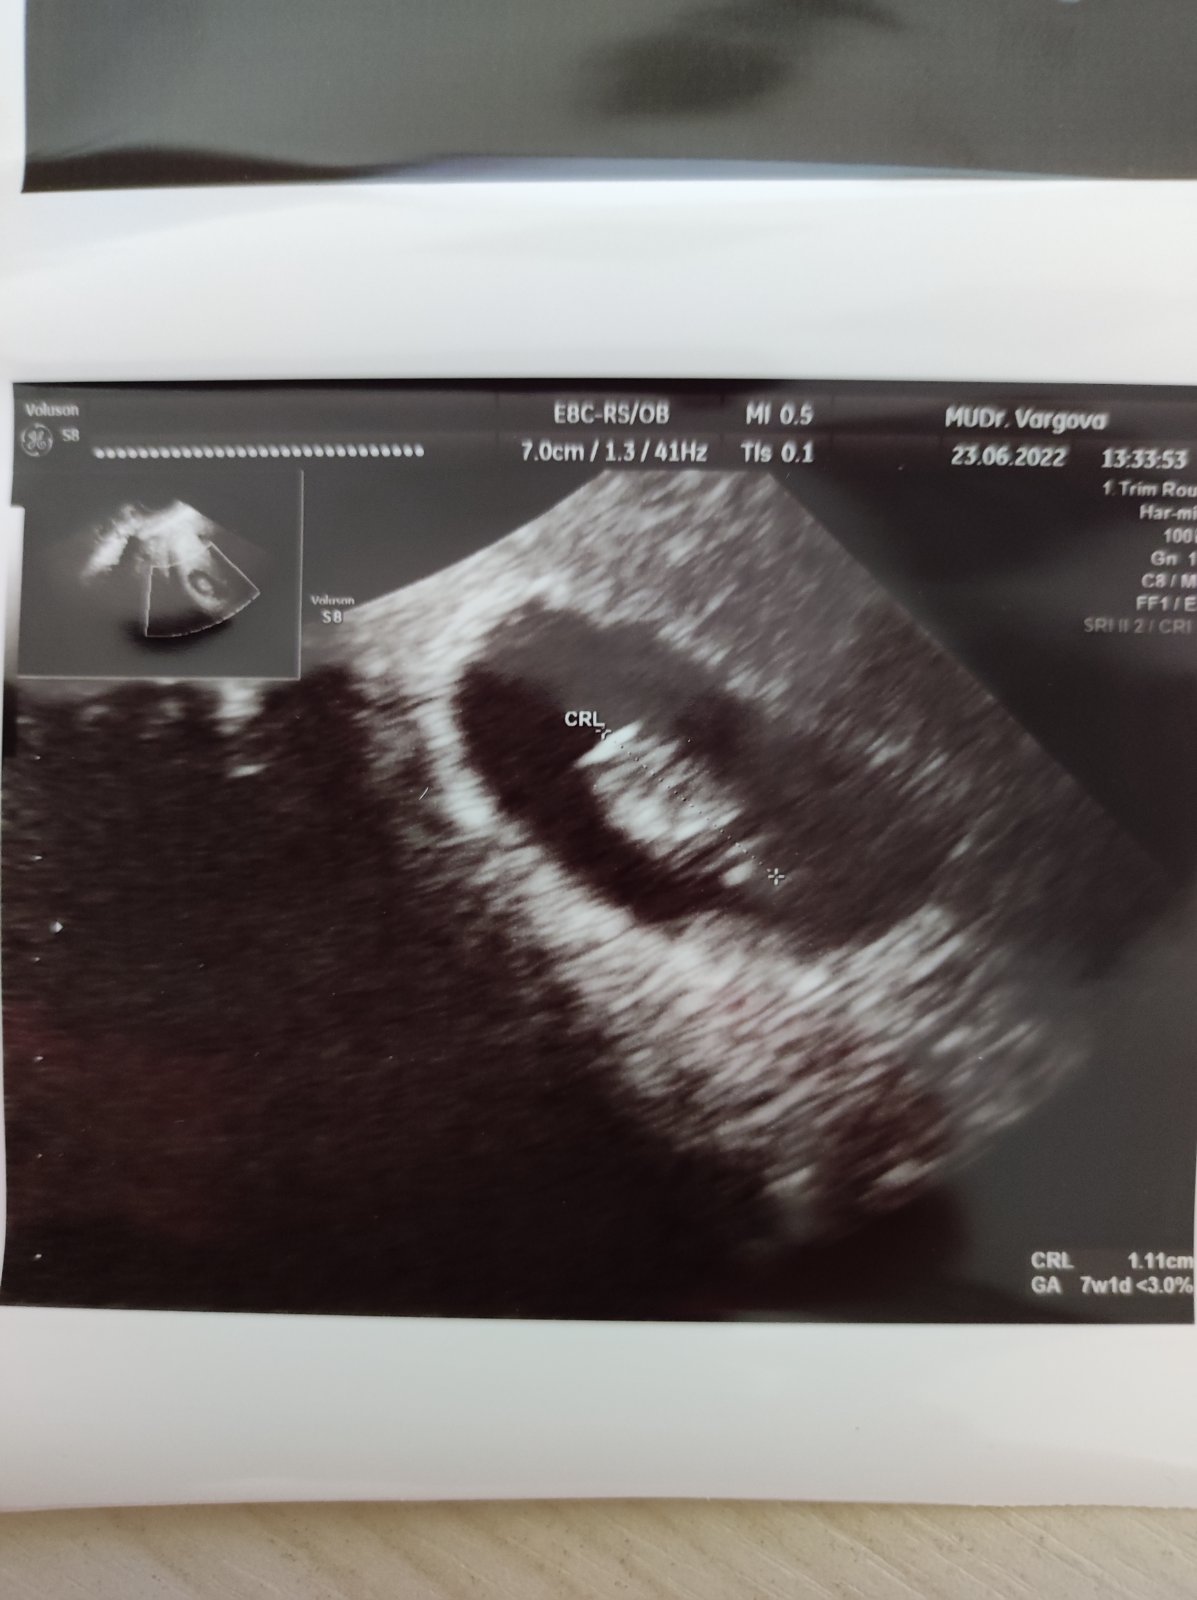

Kindervajka ako sa mate? Ja som dnes mala prvu poradnu 8+4tt dostala som tehu knizku a mam sa uz hlasit do rizikovej poradne v nemocnici kde budem rodit. Na odporucanie diabetologicky. Tak uvidime ci ma tam vezmu tam skoro. Inak mame 1.11.cm a podla sono sme.pozadu 7+1tt ale nakolko ms nemam pravidelnu a ani tie merania nie su presne nemame to riesit...